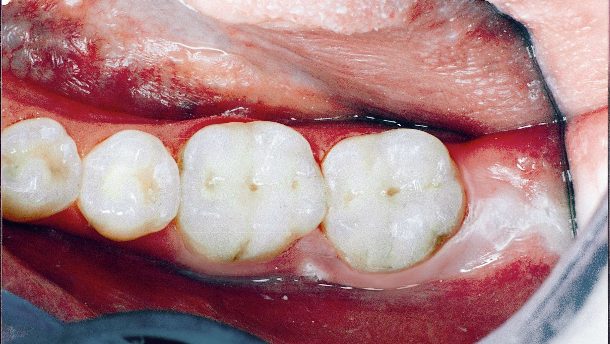

Secondo un recente studio, gli scienziati della Tufts University, vicino a Boston, sostengono di aver trovato prove del fatto che la cosiddetta Stomatite Ulcerosa Cronica (CUS), caratterizzata da ricorrenti ulcere dolorose, è principalmente causata da una reazione autoimmune del corpo che distrugge il legame delle cellule interne allo strato superficiale del tessuto della bocca.

Finora, la CUS si è manifestata principalmente in donne caucasiche di mezza età. È possibile diagnosticarla solo con una biopsia chirurgica mediante un esame di immunofluorescenza al microscopio in un laboratorio esterno.

Nei normali ambienti clinici è possibile prendere il lichen planus erosivo per via orale, un’altra, più comune, malattia cronica che colpisce le superfici mucose, considerata anche questa una malattia autoimmune.